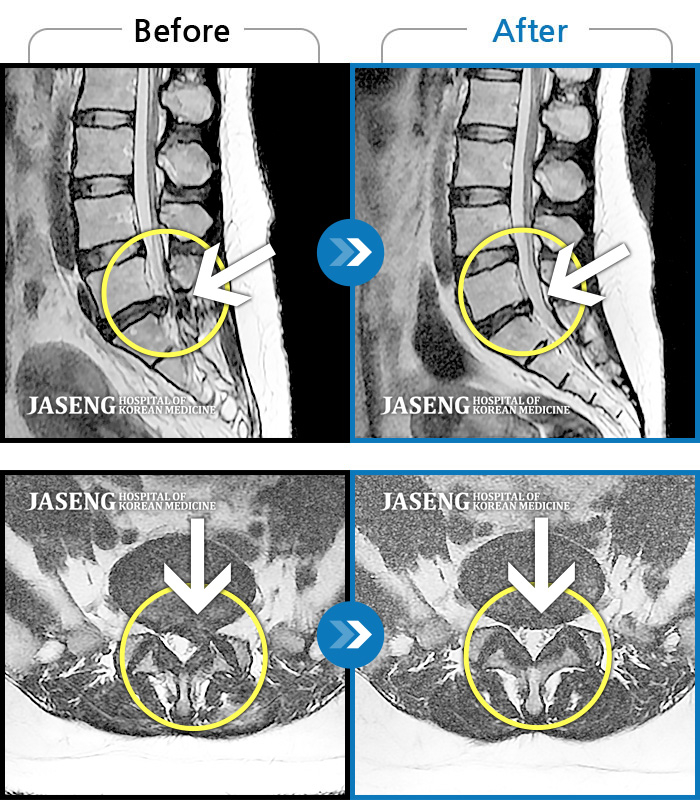

25년 1월 허리통증이 시작되고 잠을 잘수도없고 걸을 수 없을만큼의 상태가 되었을때 다시 김태용 원장님께 진료를 받고 예전 허리수술의(4번5번)(3번4번)디스크탈출증 재발과 협착증의 진단을 받고 지금까지 기나긴 여정의 입원 치료를 하며 곧 퇴원을 앞두고 있습니다.